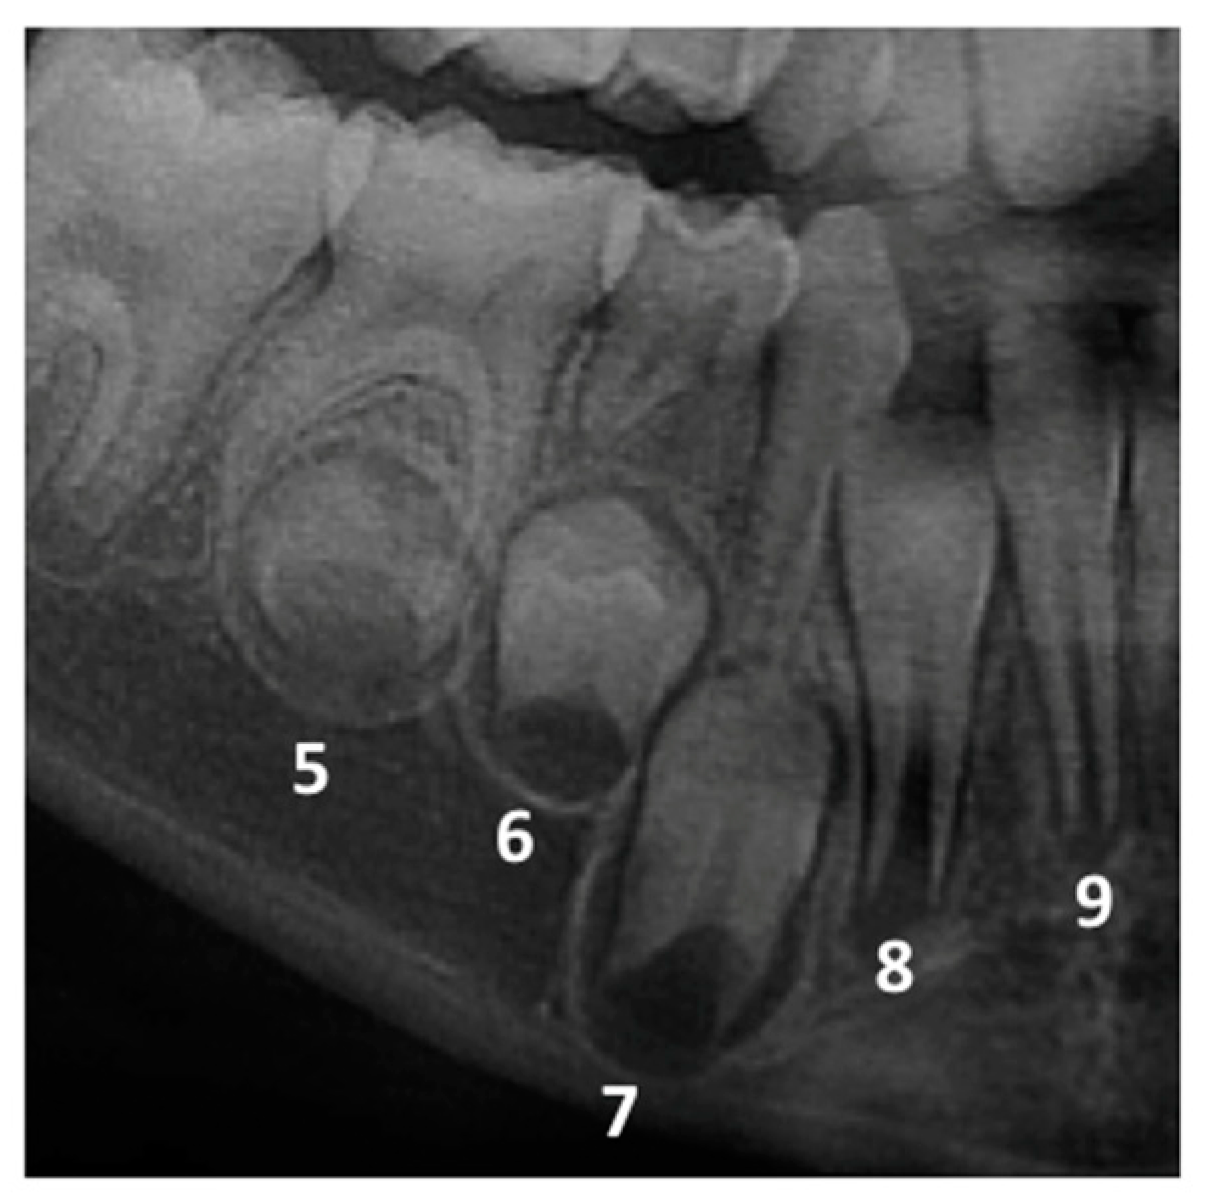

2.2. Panoramic Radiographs Evaluation and Characterization of PPT